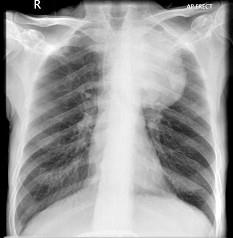

问题 56岁,男,意识错乱情绪不稳定一周,请结合胸片和CT,选出最可能的诊断 ( )

选项 A、韦格肉芽肿 B、胸腺瘤 C、错构瘤 D、胸内甲状腺肿 E、肺癌

答案 E